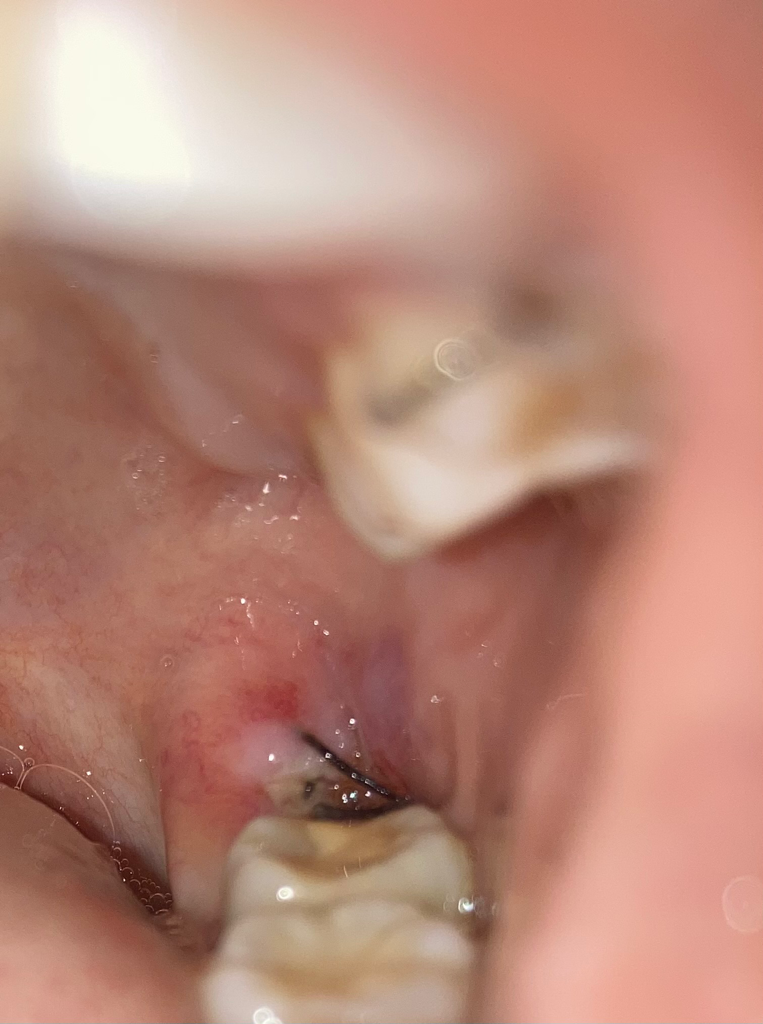

화요일 오전에 뽑았어요 매복이구요 실밥은

옆옆 어금니 쪽 까지 있어요. 통증은 귀가 넘 아파요 그 부위는 통증이 심하지 않는데 귀가 아파요 이거 잘 낫고 있는 건가요?

• 1번 째 사진

사진상으로는 크게 문제가 잇어 보이진 않고, 사랑니 발치를 하신지 얼마 되지 않아서 통증이 잇는거 같습니다. 많이 아프시면 치과에 가셔서 소독한번 받아보세요.